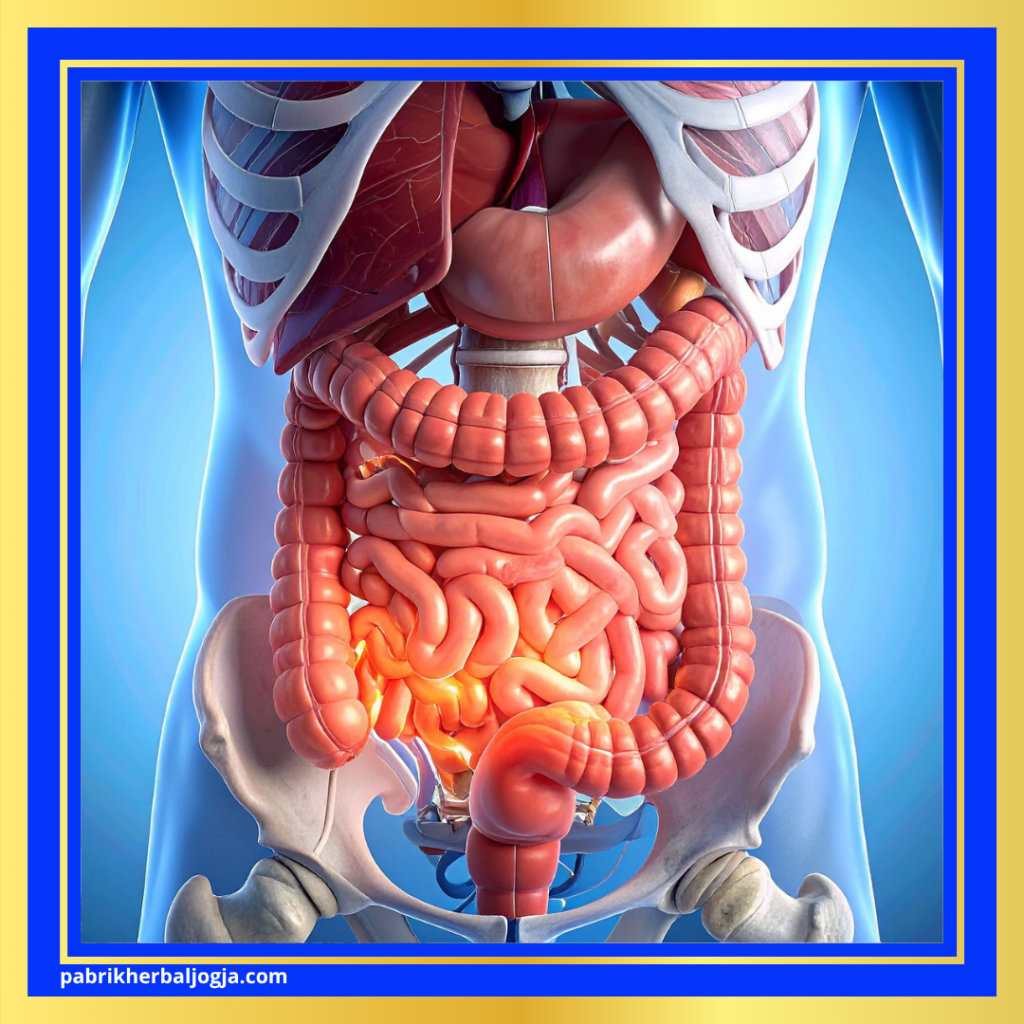

Mengenal Letak dan Fungsi Area Bawah Perut

Sebelum membahas penyebabnya, penting untuk memahami bahwa bagian bawah perut terbagi menjadi dua sisi — kiri dan kanan — yang masing-masing memiliki organ berbeda.

- Bagian bawah perut kiri mencakup sebagian usus besar, ovarium kiri pada wanita, serta ureter yang menghubungkan ginjal dan kandung kemih.

- Bagian bawah perut kanan mencakup usus buntu (appendiks), sebagian usus halus, ovarium kanan, serta saluran kemih.

Karena letak organ berbeda, penyebab nyeri di masing-masing sisi pun bisa bervariasi.